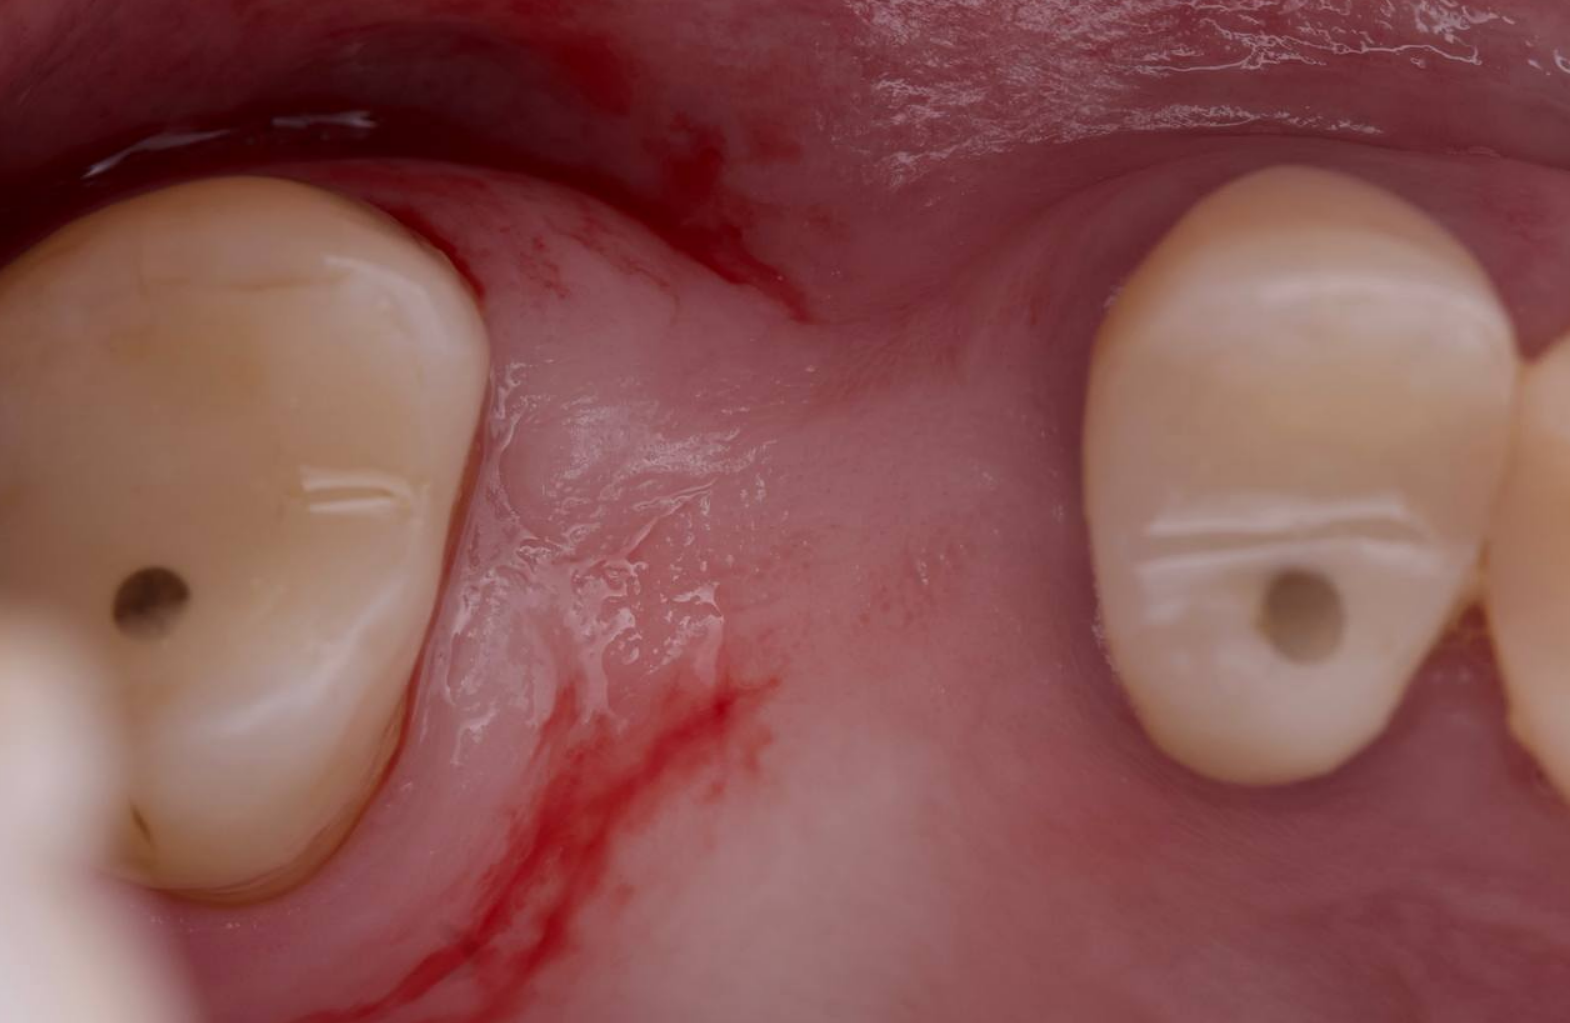

ЗСЛ + имплантация

Закрытый синус-лифтинг, выполненный вогнутым остеотомом, с показательным срезом КТ после операции.